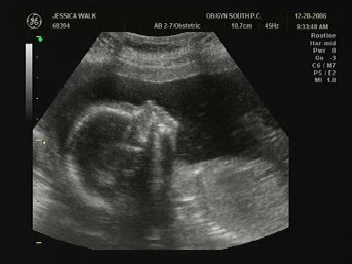

Dec 20, 2006 - Mommy and Daddy

got to see me today on the ultrasound (see pictures below). I was being very

wiggly and I waved to them. Mommy and Daddy had the technician write down my

gender and put it in an envelope. They plan on opening it on Christmas.

Baby at 20wk Ultrasound